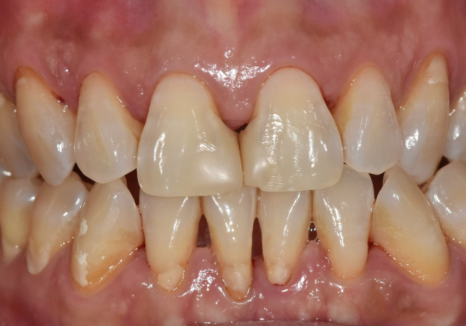

오늘 소개해 드릴 50대 환자분도

비슷한 고민으로 내원하셨는데요.

이 환자분은 젊었을 때부터

앞니 사이가 벌어져 있어

과거에 레진으로

치아 사이를 메운 경험이 있으셨습니다.

250318

치료 직후에는 큰 불편함 없이

오랜 기간 잘 사용하셨지만,

시간이 지나면서

앞니 사이로 음식물이 끼기 시작했다고

말씀해 주셨습니다.

나이가 들수록 잇몸은

자연스럽게 조금씩 내려가게 되는데,

고덕동 치과 누런 이, 앞니 사이 틈, 잘못된 관리 때문일까?

이 과정에서

잇몸과 레진으로 막아두었던 경계 부위 사이에

미세한 틈이 생기게 됩니다.

잇몸이 내려가면서 치아 사이 공간이

삼각형 모양으로 검게 보이는 현상을

"블랙 트라이앵글(Black triangle)"이라고 합니다.

실제로 1년 전 초진 사진과

최근 사진을 비교해 보니,

잇몸 퇴축이 눈에 띄게 진행되면서

블랙 트라이앵글의 크기가

이전보다 확연히 커진 상태였습니다.

240716 / 250318

이로 인해

음식물이 반복적으로 끼고,

양치가 점점 어려워지면서

식사 후 불쾌감이 계속될 수밖에 없었던 것이죠.